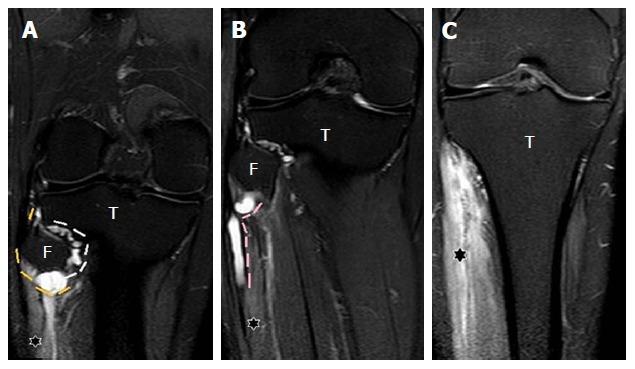

A retrospective analysis of the magnetic resonance (MR) images of a cohort of 245 patients presenting with nerve palsy involving different peripheral nerves was done. MR images were analyzed for the presence of a nerve lesion, and if found, it was further characterized as solid or cystic. The serial axial, coronal and sagittal MR images of the lesions diagnosed as INGC were studied for their pattern and the anatomical extent along the course of the affected nerve and its branches. Its relation to identifiable anatomical landmarks, intra-articular communication and presence of denervation changes in the muscles supplied by involved nerve was also studied.

A total of 45 cystic lesions in the intra or extraneural locations of the nerves were identified from the 245 MR scans done for patients presenting with nerve palsy. Out of these 45 cystic lesions, 13 were diagnosed to have INGC of a peripheral nerve on MRI. The other cystic lesions included extraneural ganglion cyst, paralabral cyst impinging upon the suprascapular nerve, cystic schwannoma and nerve abscesses related to Hansen's disease involving various peripheral nerves. Thirteen lesions of INGC were identified in 12 patients. Seven of these affected the common peroneal nerve with one patient having a bilateral involvement. Two lesions each were noted in the tibial and suprascapular nerves, and one each in the obturator and proximal sciatic nerve. An intra-articular connection along the articular branch was demonstrated in 12 out of 13 lesions. Varying stages of denervation atrophy of the supplied muscles of the affected nerves were seen in 7 cases. Out of these 13 lesions in 12 patients, 6 underwent surgery.